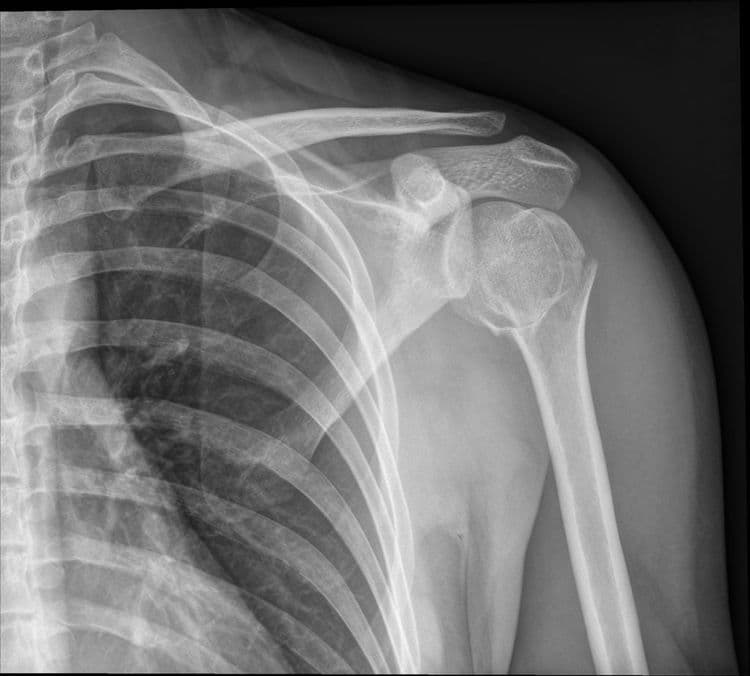

Impacted Fracture - एखादे हाड तुटते तेव्हा त्या हाडाचा हिस्सा दुसऱ्या हाडांमध्ये घुसण्याची स्थिती.